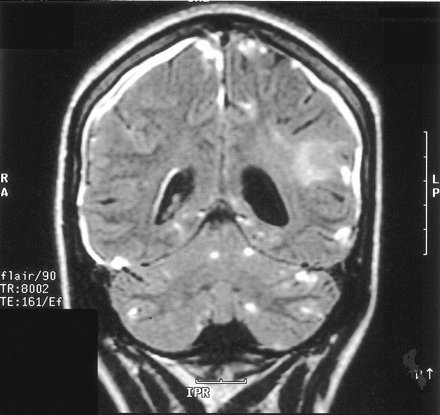

On the dermatologic examination, diffuse asymptomatic papules were found, mostly in the lower limbs. These lesions had a diameter of a few millimeters, were surrounded by a erythematous rim, and their color was pink, with a central atrophic area characterized by adherent whitish desquamation (Fig 1); a skin biopsy on the leg confirmed the diagnosis of Degos disease (Fig 2). The neurologic examination noted anisocoria, hearing loss on the left side, diffuse muscle hypotrophy, impaired finger movements, mild paresis of the right arm, paralysis of both legs, symmetrically reduced muscular reflexes, hypoesthesia, hypopallesthesia of the lower limbs, constipation, and urinary incontinence. No fever or meningeal signs were present. Brain MR imaging (Figs 3–5) showed both old and new ischemic lesions, mainly present in the left hemisphere, and numerous small nodules, localized in both the cerebral and the cerebellar cortices. A diffuse and homogeneous thickening of the meninges, with some subdural fluid accumulation, was also evident in the frontoparietal region. Ependymal enhancement was noted in the atrium of the right lateral ventricle. Hydrocephalus and venous thromboses were ruled out. Spinal MR imaging showed thinning of the spinal cord, with mild alteration of the signal intensity in the thoracic cord (Fig 6). A subtle, focal cord enhancement was found in the cervical and thoracic cord (Fig 7).

Contrast-enhanced FLAIR coronal image shows cerebral and cerebellar lesions, right ependymal alteration, and dural thickening; ischemic changes can be noted in the left parietal white matter. On the right, subtle hypointense CSF collection is recognizable among thickened meninges.